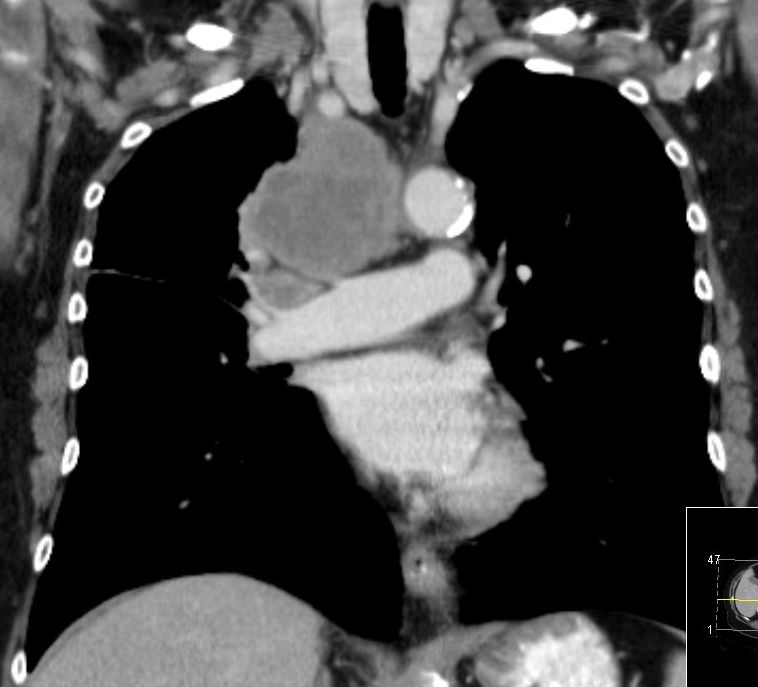

zentrales, kleinzelliges Lungenkarzinom rechter OL mit Infiltration des Mediastinums T4 N3 M1 oss ? 68jährige Patientin im reduzierten AZ und normalen EZ. Unsicherer Gang bei Kreislaufstörungen. Belastungsdyspnoe. Deutliche Leistungsschwäche. Supraklavikulargruben: links frei, rechts auffälliger Tastbefund. ![]() |

![]() | ||